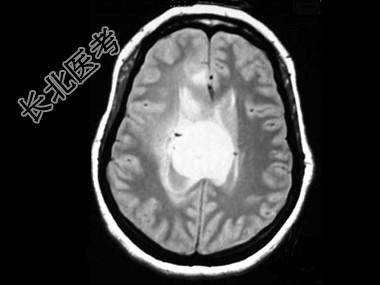

- 单项选择题女,31岁, 癫痫发作,头痛, 头晕,结合图像, 最可能的诊断是 ( )

A、脑膜瘤

B、脑囊肿

C、星形细胞瘤

D、脑膜炎

E、室管膜瘤